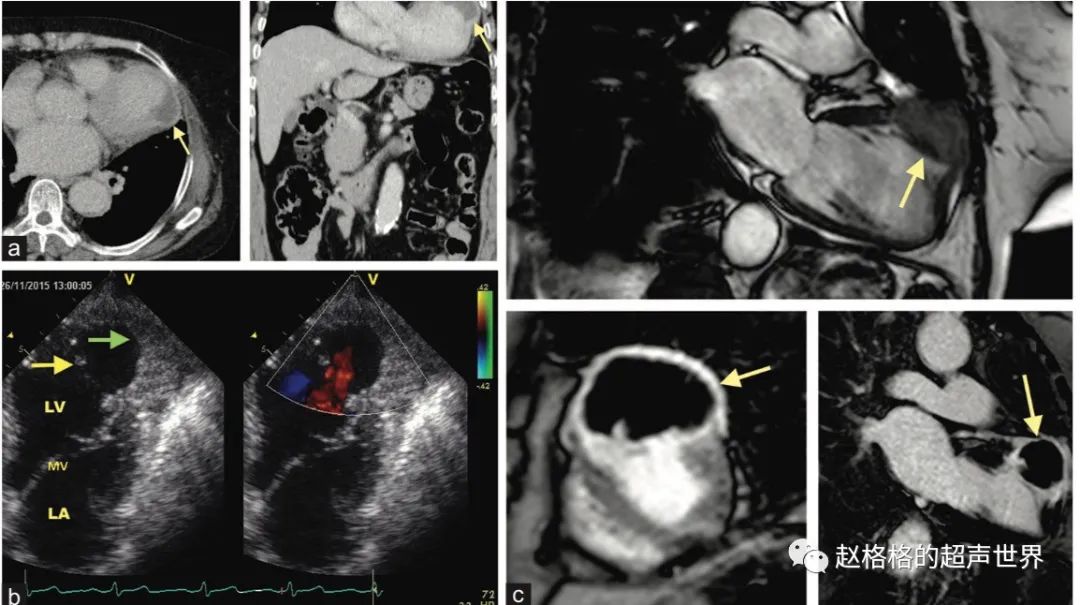

图A:左室游离壁破裂;图B:室间隔穿孔;图C:乳头肌断裂